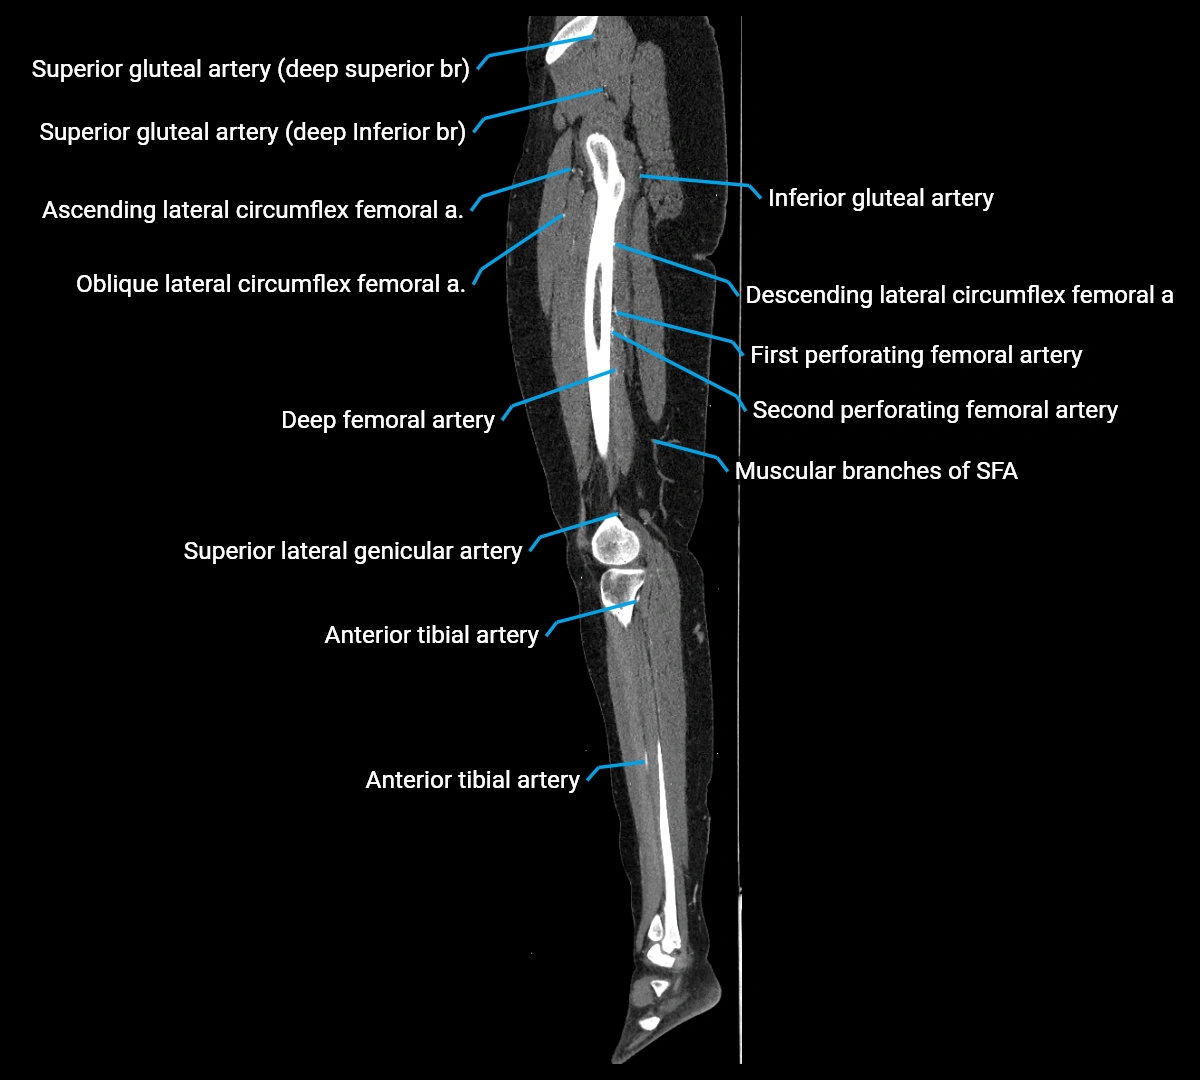

Contrast-enhanced CT (CTA):

• Gold standard for abdominal aortic imaging

• Provides excellent detail of lumen, wall, aneurysm, thrombus, and branch vessels

• Multiplanar and 3D reconstructions help in aneurysm measurement, stent graft planning, and dissection evaluation

• Detects acute rupture, traumatic injury, or occlusion with high sensitivity